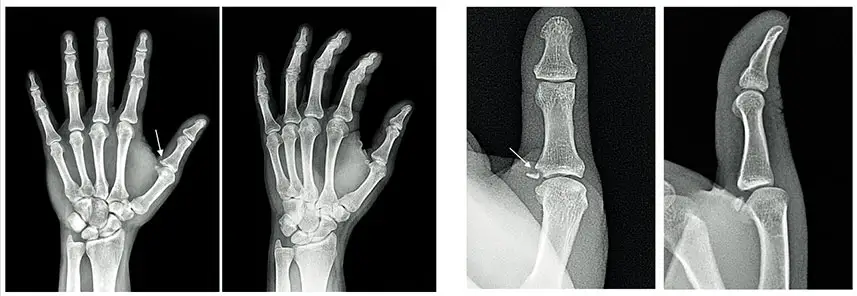

По результатам рентгенографии левой кисти врач-рентгенолог заметил добавочную тень в основании проксимальной фаланги 1-го пальца. По дальнейшим исследованиям поставлен диагноз — авульсионный отрыв костного фрагмента со смещением у места прикрепления коллатеральной связки к основанию проксимальной фаланги первого пальца левой кисти.

В соответствии с классификацией переломов первого пальца (палец егеря, палец лыжника) это перелом II типа. Требуется операция. Пациент направлен на оперативное лечение. Желаем скорейшего выздоровления и ждем на реабилитацию.